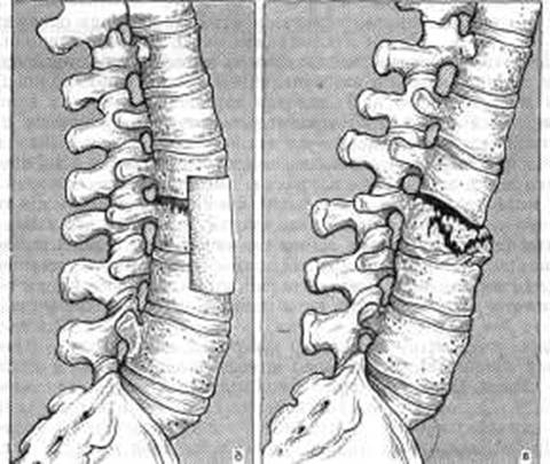

Особое внимание следует уделить компрессионному перелому позвоночника. Это очень серьезное повреждение, которое может привести к серьёзным повреждениям спинного мозга. Компрессионный перелом происходит в результате сжатия тела позвоночника. Такая травма чаще всего происходит вследствие неправильного падения на ноги, ягодицы, а также во время внезапного сгибания туловища во время выполнения спортивных упражнений.

- кифотическую деформацию;